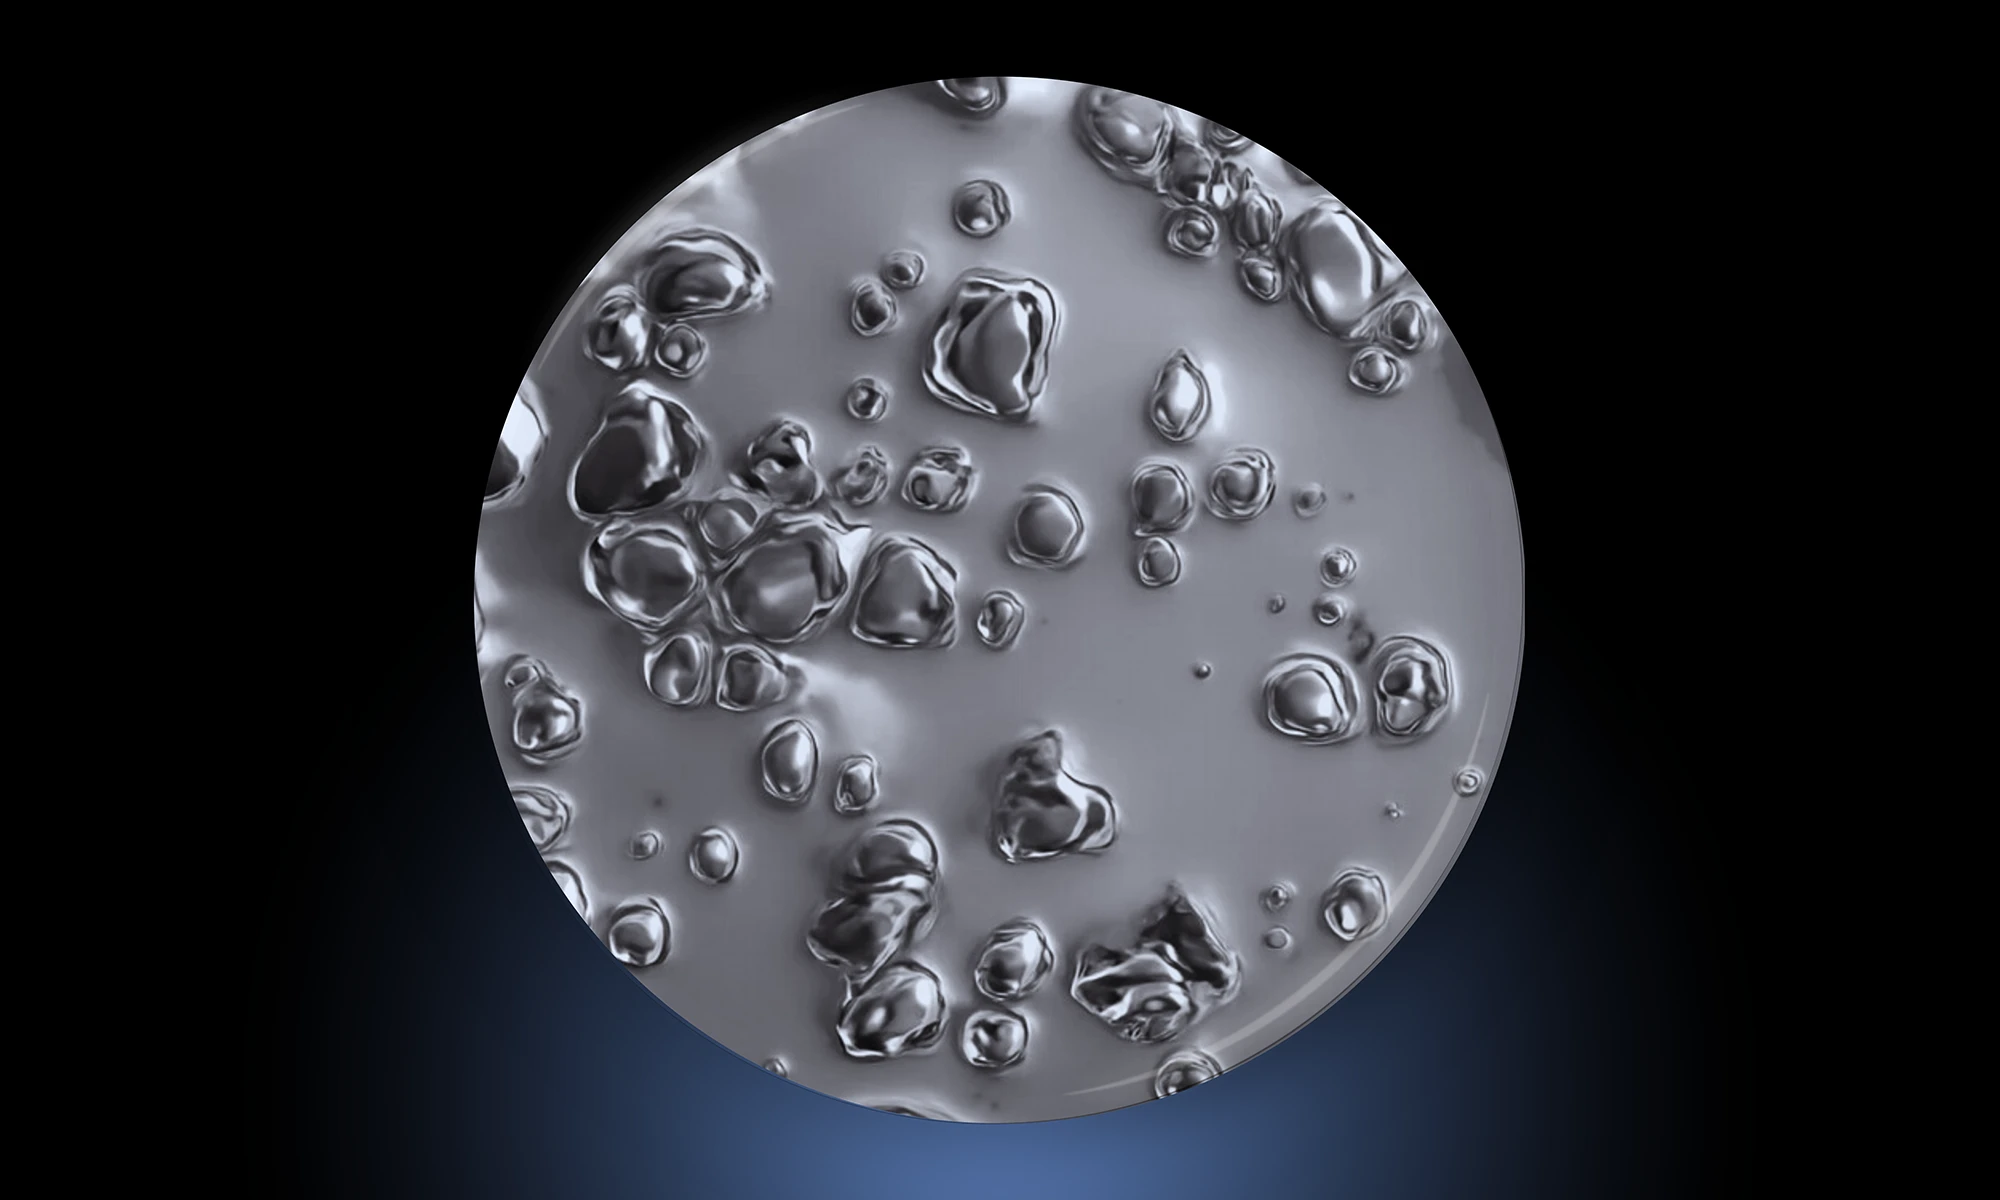

From Cells to Cures: The Revolution of the Living Drug